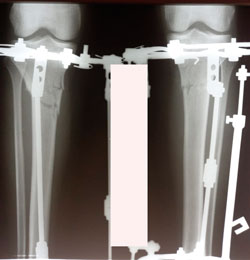

Исходник - 35 лет.

Дата операции - 22.01.2021